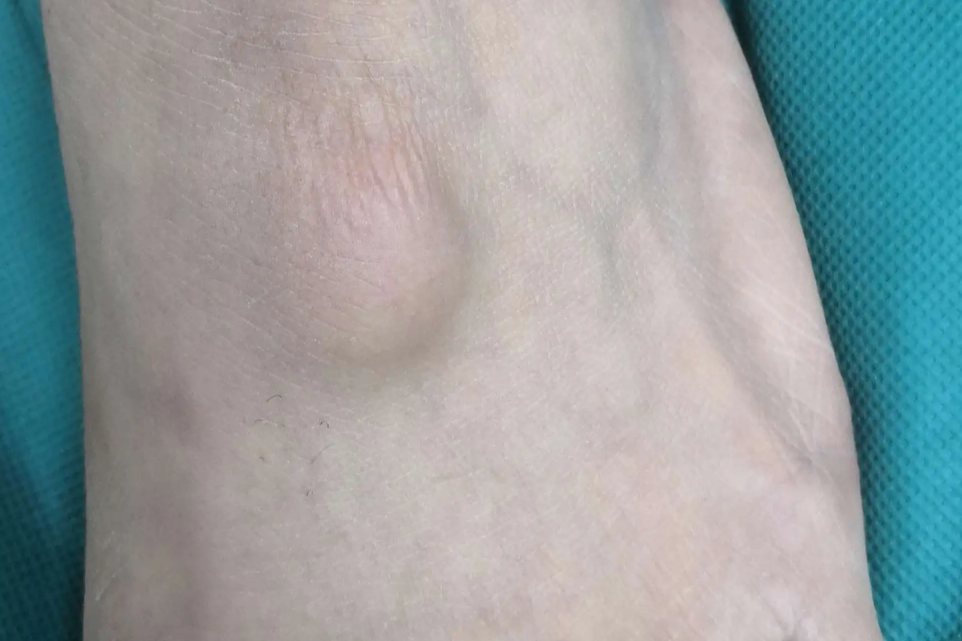

膝盖边上凸起一个软包可见于脂肪瘤或腱鞘囊肿。

腱鞘囊肿

腱鞘囊肿的临床表现为皮下浅表的半球形包块,隆起于皮肤表面,大小不一,表面光滑,有韧性,与周边组织无粘连,边界清晰,一般无明显压痛。